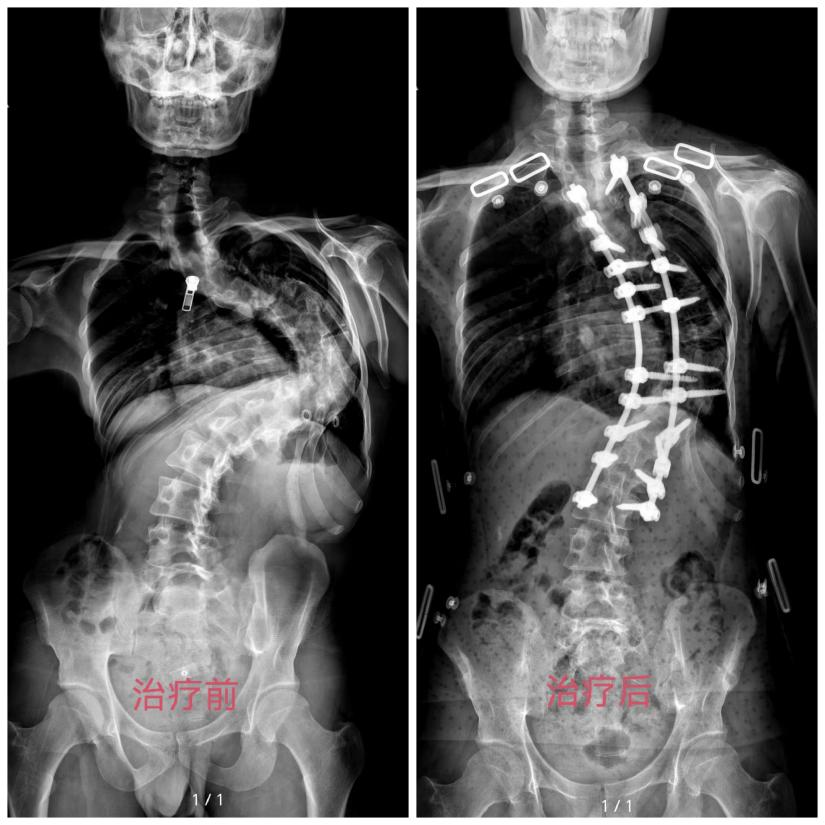

而针对病情最为复杂的两名重度脊柱畸形患者,以萧山区中医院为代表的医疗团队则制定了更为审慎的个性化方案——“头盆环持续牵引+二期截骨矫形”阶梯治疗。在近七个月的治疗周期里,医院集结骨科、麻醉科、康复科等多学科MDT团队,从术前功能锻炼、营养支持,到术中精准保障、术后康复重塑,实施全周期管理。两名患者佩戴外固定支架经历了长达数月的渐进式牵引,每一次调整、每一次查房,都倾注着杭州医护团队的悉心关怀与专业坚守。

功夫不负有心人,漫长的牵引治疗为高风险矫形手术奠定了坚实基础。近日,在萧山区中医院多学科团队的紧密协作下,其中一名脊柱畸形患者已成功完成高难度矫形手术,脊背挺直,效果良好。而另一名仍在牵引治疗的患者,矫正效果同样显著,各项指标持续向好,预期不久后也能顺利接受手术,迎来属于自己的“挺直时刻”。